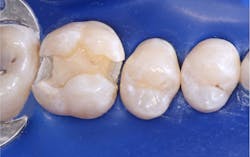

This is a well-known procedure, but it’s often confused with liners or bases. I have observed that almost all restorative dentists provide indirect pulp capping for their patients. The size and location of the dental pulp varies significantly depending on patient age and the extent of previous restorative treatment causing pulp response and reduction in pulp size (figure 1). When excavating caries, the ideal goal is to remove all observable caries without exposing the pulp. Often, the following situations occur in a typical day of practice: removal of the soft caries, dentin is hard to remove with an excavator, stained tooth structure remains, and the operator’s knowledge of dental anatomy and a radiograph indicate that a pulp exposure will occur if excavation is continued. An indirect pulp cap is placed on the deepest portions of the tooth preparation (figure 2).

A direct pulp cap is performed when the pulp is exposed during caries excavation, and it’s bleeding. The various definitions of when and if to do a direct pulp cap are extremely variable. Based on hundreds of direct pulp caps with impressive success, these are my criteria for performing a direct pulp cap (figure 3):